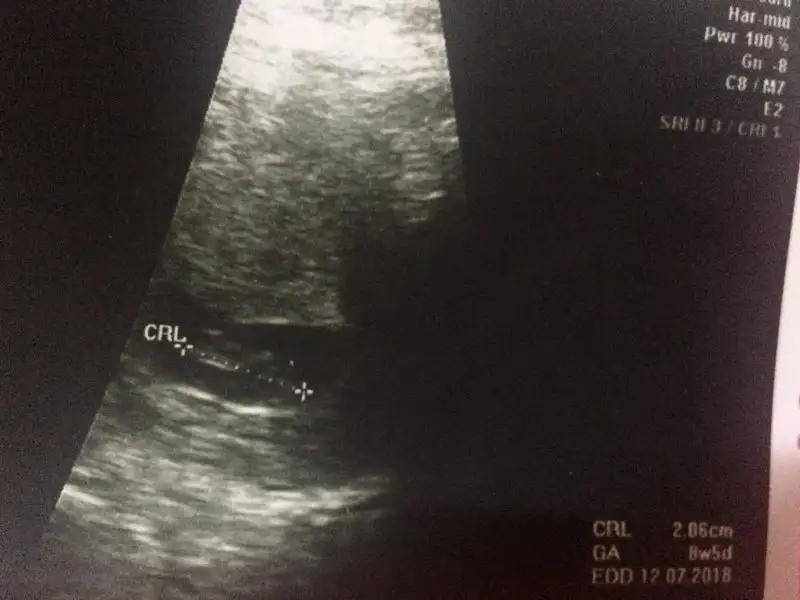

Ay inanmasamda severim böyle şeyleri karbonat lavabo açıcı vs bende yapim benim bebek sağ tarafta ne oluyor acaba ultrasonu ekledim :)

Sonunda yükleyebildim sabahtan beri bu da benim kesem